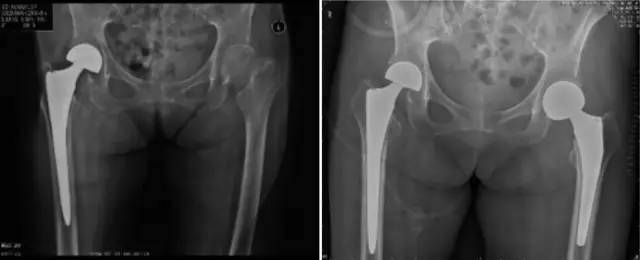

各种晚期骨关节病的关节置换手术治疗是北京清华长庚医院关节外科中心的一大特色,包括股骨头坏死、髋膝骨关节炎、类风湿关节炎、强直性脊柱炎、髋关节发育不良、关节强直、超过80岁的超高龄股骨颈骨折患者的关节置换手术等,我中心在人工关节初次置换及翻修上作了大量工作,置换的难度和手术效果方面已达到国际先进水平,导航下全膝关节置换术:大大提高膝关节置换手术的精确度。

局限性关节置换手术(UKA)

全膝关节表面置换手术(TKA)

铰链式人工膝关节置换手术(HK)膝关节周围韧带严重破坏

国内首例膝关节置换术后Felix IIB型胫骨假体周围骨折翻修术